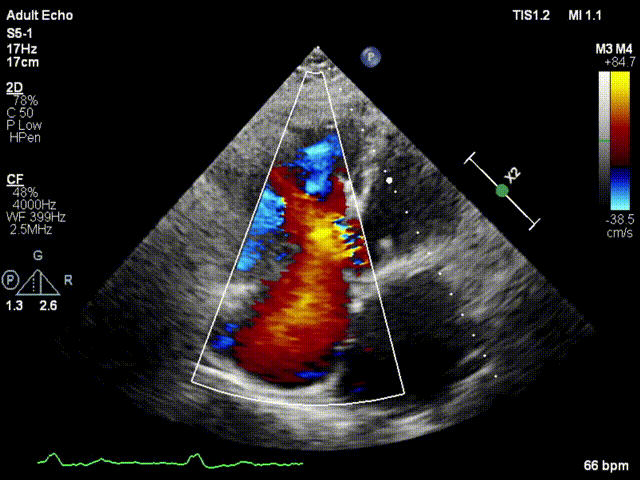

本次接受治療的患者是一名74歲的女性,14年前因風濕性心臟病行二尖瓣生物瓣植入術,合并房顫。近3年來反復因腹脹、納差、下肢水腫入院,藥物治療欠佳。心臟超聲顯示三尖瓣極重度反流(有效反流口面積:0.76cm²,反流容積:79ml),繼發性右房室增大及上、下腔靜脈增寬(右房上下徑*左右徑:52*41mm,右室左右徑:46mm,下腔靜脈:29mm),右室收縮功能正常,肺動脈收縮壓 43mmHg,左心室射血分數73% 。患者既往開胸手術史,術前評估STS 評分為7.02分,CRS 9分,無法接受體外循環下三尖瓣外科手術。面對這一傳統治療無法解決的困境,葛均波院士及其團隊周達新教授、潘文志教授、張源博士、陳莎莎博士及心超室的潘翠珍教授、李偉教授經過討論決定,采用創新的Lux-Valve Plus系統為患者進行經血管三尖瓣置換。

手術在患者全麻狀態下進行,采用經右側頸靜脈作為入路,將裝載有人工瓣膜的輸送器緩慢推送至右心房;并在經食道超聲和DSA的引導下小心調整輸送器角度,將輸送器送入右心室;逐步釋放瓣膜錨定裝置和盤片,調整瓣膜位置后,錨定瓣膜完成植入。術后右房壓明顯下降,從術前的25/10(16) mmHg降至術后即刻的12/7(10) mmHg,術后超聲提示人工三尖瓣同軸性良好,固定牢固,無反流及瓣周漏,手術室即刻拔除氣管插管。